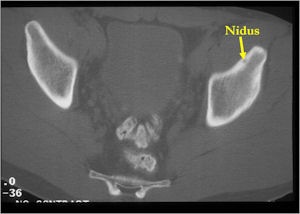

CT Scan:

- Well defined nidus with a smooth peripheral margin; +/- mineralization (CT more sensitive than XR and MRI for detecting mineralization); CT is better for detecting nidus in presence of exuberant sclerosis